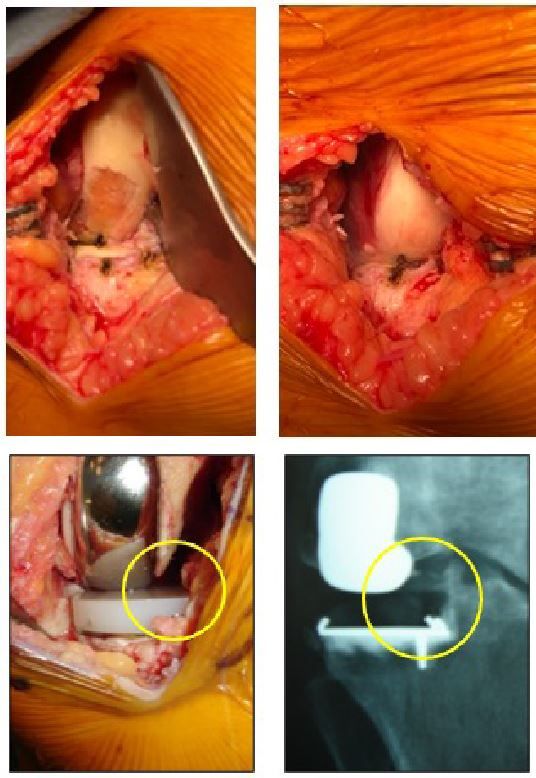

Depending on whether the damage is in one or two compartments (medial tibiofemoral and/or patellofemoral osteoarthritis), the surgeon may decide to perform an additional medial UKA or patellofemoral replacement, [27–31] without revising the lateral UKA, or perform revision surgery to a TKA.[32,33]. With a well fixed all-polyethylene tibial component, and unless there is sepsis, the tibial component does not automatically have to be removed. In these cases the TKA metal tibial baseplate can be fixed to the well fixed polyethylene tibia component, possibly after recutting it with an oscillating saw [34]. Although not a significant finding of our study, the risk of surgical revision tends to rise among young patients (age < 50). These cases often involve patients with post-traumatic osteoarthritis or status post meniscectomy, with high functional demands and a high life expectancy on the date of surgery.

The satisfaction rate with UKA is very high among elderly patients, despite moderate functional scores. The revision rate is low, and the primary aim is pain relief in a population wanting to regain their autonomy and avoid complex or repeated surgery. The valgus morphotype is commonly associated with lateral condylar hypoplasia: this is an ideal indication for resurfacing UKA. By limiting the bone removal during femoral preparation, the condylar implant will occupy a relatively larger space and the mechanical femoral angle will be closer to 90°, as clearly shown in our study. The surgeon should account for this particular anatomical feature of the lateral compartment, either by using a resurfacing implant (variable thickness condylar components could be a good technical solution for these cases), or by using a cutting implant and a minimal distal cut. This lowers the risk of bringing the joint line in valgus position (Fig. 19). If there is no condylar dysplasia, in patients with a neutrally aligned limb suffering from lateral tibiofemoral osteoarthritis secondary to lateral meniscectomy for example, we believe that cutting implants are indicated to avoid any overcorrection. In our study, there was however no effect on overall axis or survival.